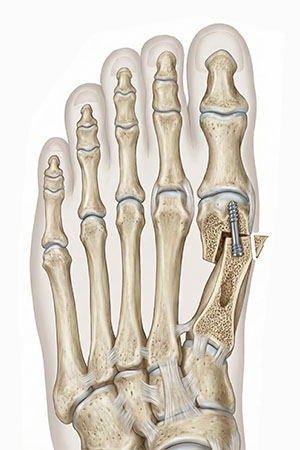

뼈만 깎는 수술은 시간이 지나면 다시 휘어질 가능성이 높습니다. 본원은 엄지발가락을 잡아 당기는 인대와 힘줄을 정교하게 풀어주는 유리술을 먼저 시행하여 재발 요인을 근본적으로 해결합니다. 이후 특수 나사를 이용해 뼈를 견고하게 고정함으로써, 교정된 정렬이 흐트러지지 않도록 유지력을 극대화합니다.

• 04

교정된 뼈를 특수 나사로 견고하게 고정하여 수술 직후의 완벽한 정렬을 안정적으로 유지하고 빠른 회복을 돕습니다.